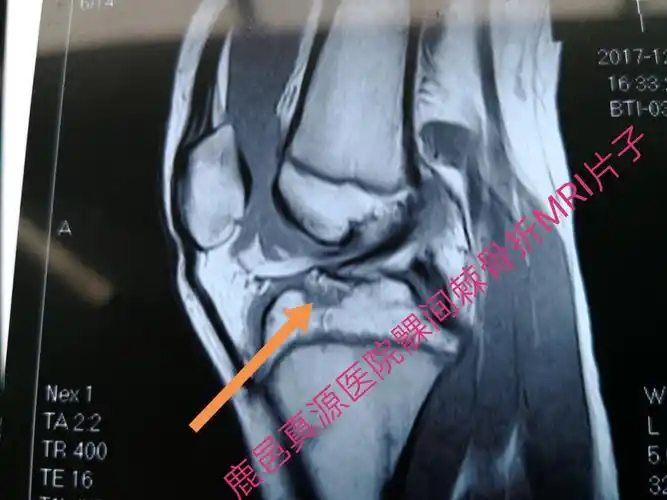

胫骨髁间棘骨折术前mri片子,显示髁间棘骨折!

疼痛,肿胀,活动受限,在外院做膝关节x线检查发现是左侧胫骨髁间棘骨折